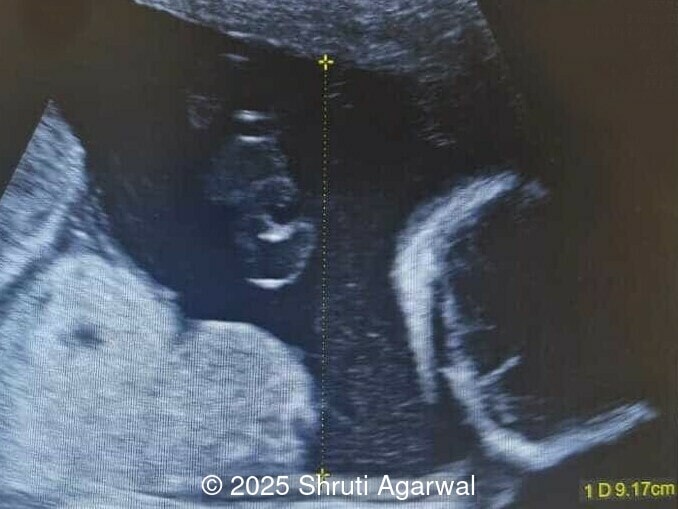

We present a case of fetal anemia due to a giant chorangioma.

- Image 1,2: Large placental tumor is identified with internal vascularity

- Image 3: Cardiomegaly

Placental chorangioma is the most common neoplasm of the placenta occurring in approximately 0.6% of all pregnancies [1]. In most cases, the tumor is less than 5cm in size and asymptomatic [2]. Chorangioma is considered a hamartoma or hyperplastic capillary lesion rather than a true neoplasm due to its inability to metastasize, and the tumor has no malignant potential [3]. Chorangiomas are usually found in the third trimester as a solitary nodule in the placental parenchyma. On gross examination, the chorangioma is well-circumscribed, without a fibrous capsule, and sharply demarcated from the surrounding placental parenchyma by a single or double layer of chorionic epithelium. It tends to have fleshy, congested, red to tan colored surface [4]. The most common location is in the fetal surface of the placenta, in proximity of the umbilical cord insertion. A larger tumor is usually attached to the chorion, which is a less perfused area. A few cases have been reported on the maternal surface, replacing the whole or some part of the placental lobe [4,5]. Chorangiomas tend to arise in areas of hypoperfusion. A hypoxic state is thought to lead to active proliferation of connective tissue and growth of villous capillaries mediated by vascular growth factors [6]. Pre-eclampsia, high-altitude, and fetal anemia have been associated with chorangioma, suggesting that decreased oxygen tension may play a role in the pathogenesis [7,8].

Prenatal diagnosis depends on ultrasound, however, chorangioma can cause an increase in maternal serum alpha-fetoprotein [3]. Ultrasound examination reveals a hypo- or hyperechoic, well-circumscribed mass, which is usually located underneath the chorionic plate near the umbilical cord insertion, and often protrudes into the amniotic cavity. Color Doppler demonstrates large vascular channels around and within the tumor [6,9]. In cases of giant chorangiomas, echocardiography should be performed to assess cardiac function and measure fetal middle cerebral artery peak systolic velocity for diagnosis of fetal anemia. Regular ultrasounds with Doppler studies are used to monitor tumor size, fetal growth, amniotic fluid volume, and signs of fetal anemia or heart failure. The frequency of exams is based on tumor size and associated complications. With small tumors, assessment may occur every 3-4 weeks, whereas in large tumors, the ultrasound scan may be done every 1-2 weeks [3]. These regular assessments can diagnose conditions that require intervention, such as polyhydramnios, hydrops, or hemolytic anemia.